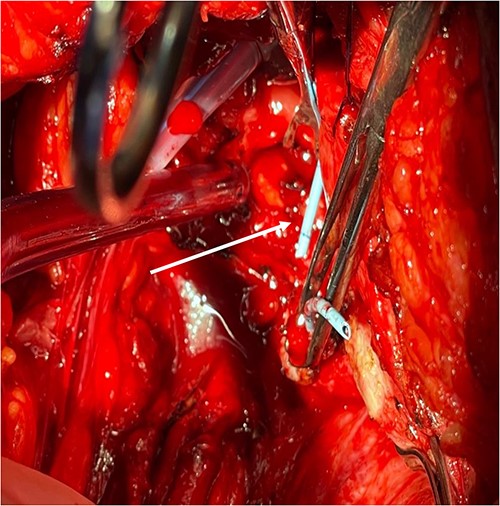

A 54-year-old female patient with a history of recurrent urinary tract infection (UTI) was admitted electively to the hospital as a case of VVF for repair. Her chief complaints were intermittent lower abdominal pain and urine leakage for ~1 year. Gynecological examination was unremarkable. She had a history of Dysfunctional Uterine Bleeding that was managed eventually by total abdominal hysterectomy with bilateral salpingo-oophorectomy. Unfortunately, bladder injury was confirmed intraoperatively. Since then, the patient started to complain of persistent urinary incontinence and urine coming out of the vagina. A total of 6 weeks later, Computed Tomography (CT) cystography was done, and it confirmed the presence of a low-lying VVF for which the patient underwent first repair. The surgery outcome was undesirable since the patient had a recurrence in ˂1 month. Moreover, postoperative CT cystography confirmed recurrence as it showed a VVF extending between the upper vagina and upper posterior wall of the bladder. After admission, preoperative work-up was done. At that time, the urine culture turned out to be positive for Escherichia coli. Therefore, the patient was managed initially with culture sensitive IV antibiotic and foley catheter. The patient was planned for surgery once the urine culture was negative. At the beginning, a diagnostic cystoscopy was performed and revealed highly suspicious areas in the left lateral and posterior wall of the bladder suggesting a fistula. Afterward, a vaginoscopy was done and showed calcified stitches along with stone (Figs 1 and 2). The stone and the stitches were removed (Fig. 3). The fistula tract then was cannulated with a guidewire (Fig. 4). A clear connection was seen between the vagina and the bladder. Afterward, the plan was to proceed with the repair. Lower midline incision was made; extensive adhesion was noted after opening the peritoneum. Despite the adhesion, bladder dissection was successful. The posterior aspect of the bladder wall was dissected and separated from the vagina with extreme difficulty. After that, a longitudinal cystotomy was done and the fistula tract was completely excised (Fig. 5). The vaginal wall was closed using 3-0 Vicryl and the bladder closed in two layers with 2-0 and 3-0 Vicryl. Unfortunately, due to the extensive adhesion, a small (2 cm) in diameter rectal injury occurred due to traction and was managed properly by general surgery. Finally, a drain and a large transurethral catheter were placed. Postoperatively, the patient initially complained of mild generalized abdominal pain and vomiting. The patient had no complaints upon discharge, and the plan was to keep the patient on the foley catheter. A total of 3 weeks later the patient was seen in the clinic, and she underwent a cystourethrogram, which turned out to be unremarkable. The patient had a successful outcome with no sign of recurrence.

Fistula tract is cannulated with a guidewire as pointed in the arrow.